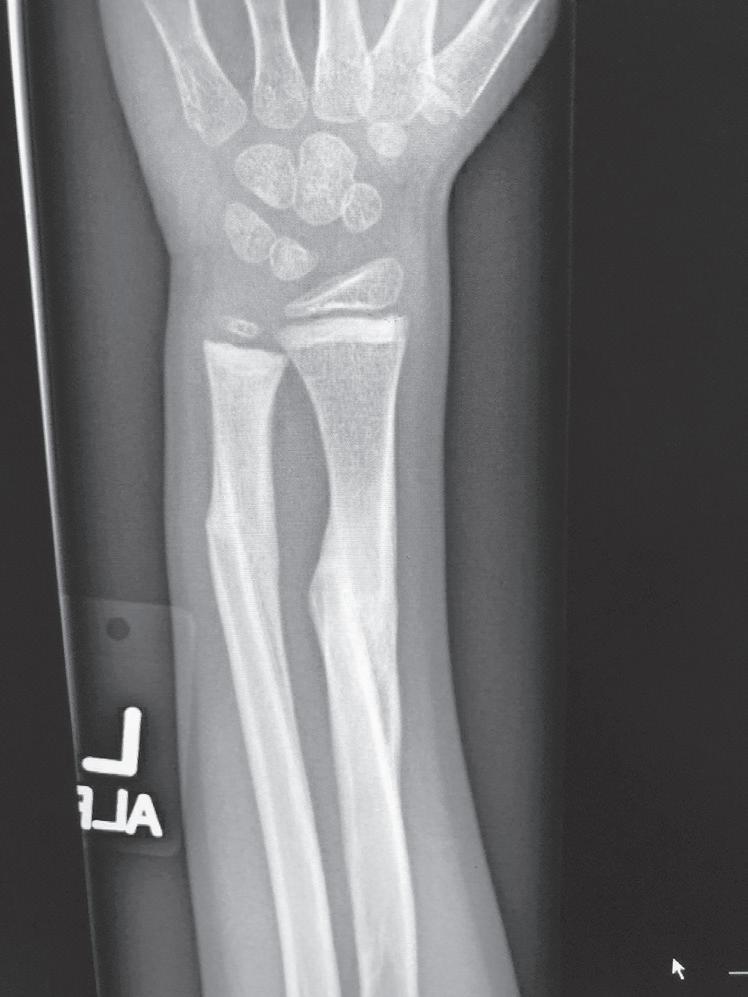

REMODELING AFTER A FRACTURE IN CHILDHOOD

The remodeling ability of bone in children may make reduction accuracy less important than it is in adults. Remodeling is a commonly used term in pediatric fracture care, implying that the child has the ability to straighten and correct residual deformity with growth. This capability depends not only on the mechanisms of bone remodeling described earlier during the remodeling phase of fracture healing (Wolff’s law) but also on reorientation of the physis by asymmetric growth after a fracture (Hueter-Volkmann law or Delpech’s law). Younger children have greater remodeling potential. The amount depends on the age of the child, location of the injury in the bone (proximity to the physis), degree of deformity, and whether the deformity is in the plane of motion of the adjacent joint.3,65,66 Clinical judgment and experience are required to guide decision-making regarding defining “acceptable” reductions, but obtaining the best reduction possible during initial treatment is advisable because it will lessen reliance on remodeling. Remodeling does not occur in displaced intraarticular fractures; thus reduction, usually by open methods, is needed. In children, remodeling is often relied on for the treatment of proximal humeral and distal radial injuries because these physes contribute greatly to the length of the respective segment, and the joints have wide ranges of motion. Remarkable remodeling has been documented in cases of these fractures (Fig. 1.4).

Remodeling may occur readily in the plane of a joint (Fig. 1.5), but it occurs far less readily, if at all, in children with rotational deformity or angular deformity not in the plane of the joint.14,65,66,69 Abraham67 studied the remodeling potential of immature monkeys and found that remodeling occurred at the growth plate and along the concavity of the shaft deformity, with minimal resorption on the convexity of the shaft. Diaphyseal remodeling and physeal reorientation with growth contributed similar amounts to the degree of remodeling. In femoral shaft fractures in children, 75% of the remodeling of angular deformities takes place in the physis, and 25% comes from appositional remodeling of the diaphysis.70 The physis adjacent to a fracture realigns itself with asymmetric growth to become perpendicular to the forces acting through the bone, and most authors believe this is the primary mechanism for remodeling.66

Significant angulation in the midportion of long bones is not usually acceptable and does not remodel very well, depending on the age of the child. In children younger than 8 years, residual angulation is more acceptable. If the angulation is less than 30 degrees and is within the plane of the joint, remodeling toward normal alignment can be expected.2,19 The potential for remodeling to an acceptable functional and cosmetic outcome depends on many factors, including which bone is fractured, how close the fracture is to a joint, the orientation to the joint axis, and the amount of growth remaining for the child.66 Side-to-side (bayonet or

Fig. 1.4 Anteroposterior of a 9-yearold with a distal radius fracture that was pinned in poor position (A), now 4 weeks out from pinning (x-ray after pin removal). Anteroposterior of the same distal radius fracture (B) at 12 months from the injury with complete remodeling. Anteroposterior of a proximal humerus fracture in an 11-year-old at the time of injury (C) and at 6 months (D). Similar to the distal radius, these anatomic locations have tremendous remodeling potential secondary to the large contribution of growth from adjacent physes.